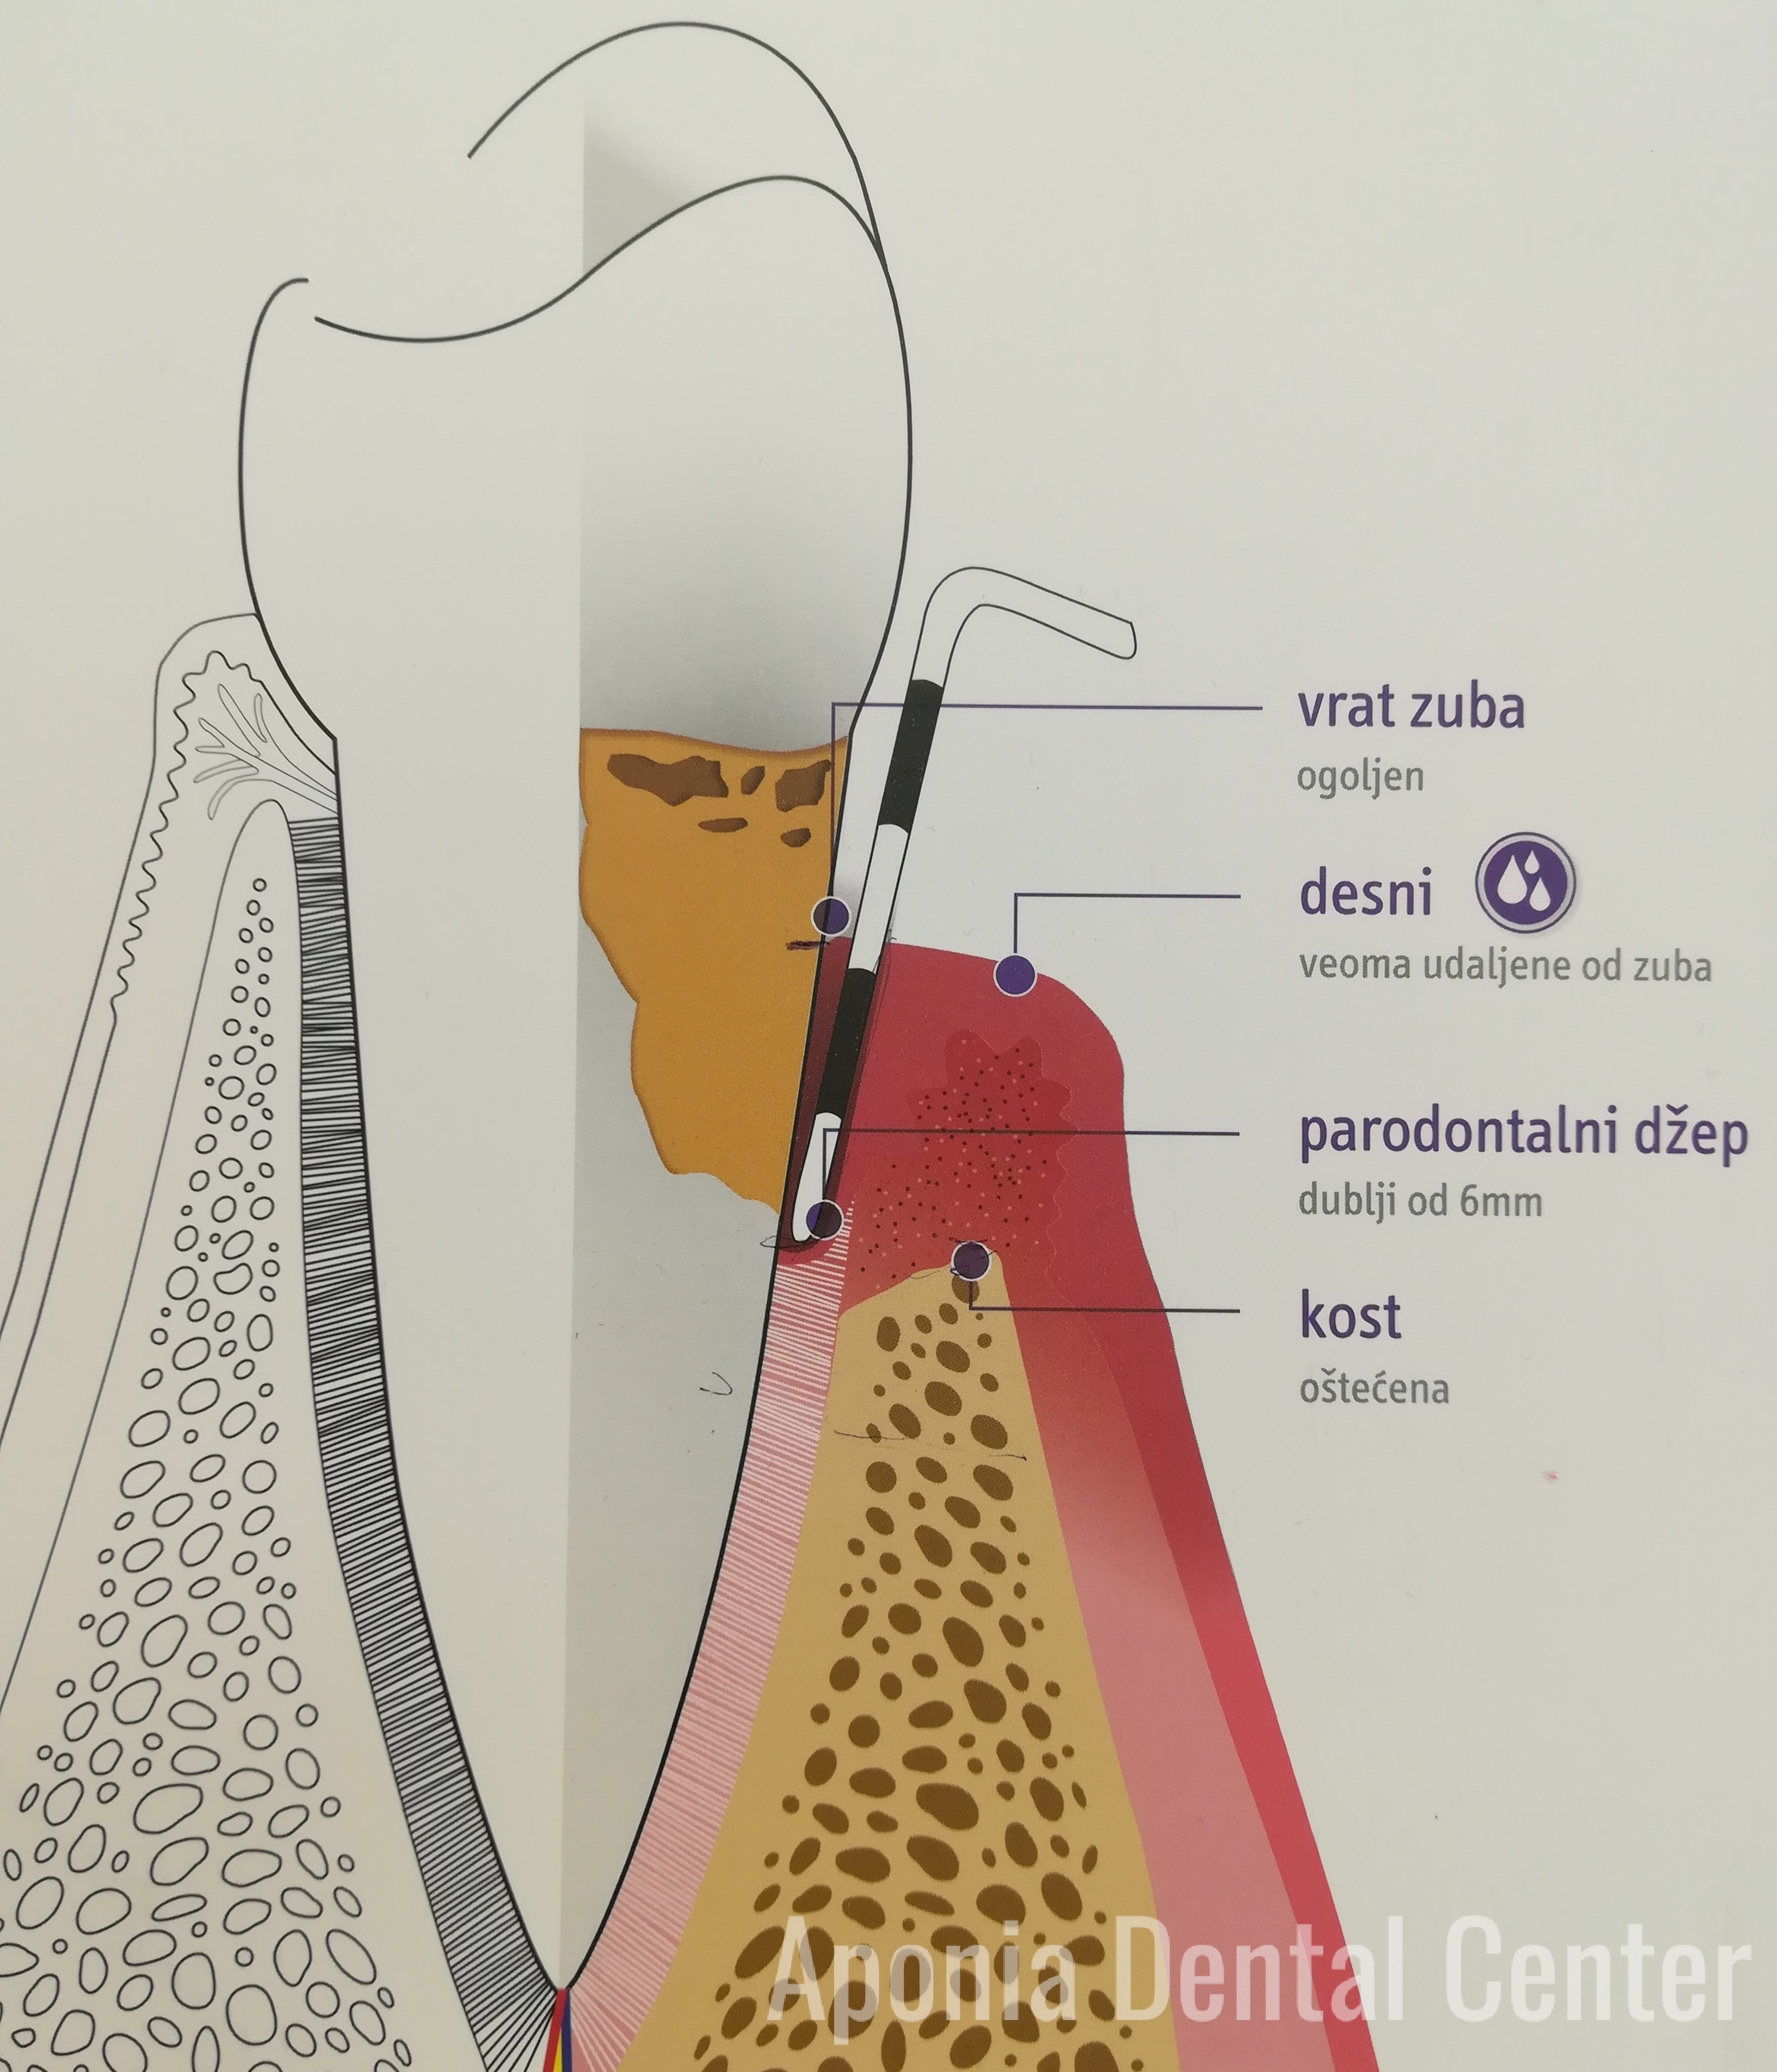

S obzirom na lokaciju umnjaka, teže ih je održavati i prati. Vrlo često se dešava da nema mesta da izniknu, pa svojim rastom guraju susedne zube i prave teskobu, prednji zubi počinju da se krive. U takvim slučajevima, dobro je izvaditi ih što je pre moguće, kako bi se sprečili potencijalni problemi, kao što su bolovi, infekcija, nošenje fiksne proteze. Kada i kako će umnjaci biti izvađeni zavisi od problema koji imate sa njima.

Glavni problemi vezani za umnjake su nemogućnost njihovog potpunog nicanja tj. pojava impakcija ili poluimpakcija tih zuba.

Impaktiran zub podrazumeva zub koji nije nikao, koji se ceo nalazi u viličnoj kosti, zato što mu je normalan put nicanja ometen. Poluimpaktiran zub je zub koji je delimično vidljiv u usnoj šupljini a delimično prekriven mekim tkivom i/ili koštanim tkivom.

Impaktirani zubi mogu rasti u raznim polozajima koji nisu pravilni sa ostalim zubima. U slučaju “dislokacije”, umnjak može rasti u stranu, pritiskajući korene susednih zuba i prouzrokujući velike bolove. Ipak, ako raste daleko od zubnog niza može mirovati i u tom slučaju ga samo treba redovno kontrolisati.